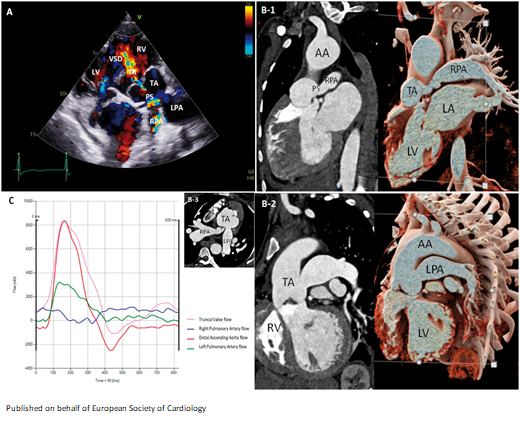

Anomalous origin of the LCX from the PA associated with non-compaction of the left ventricle: usefulness of #MultimodalityImaging bit.ly/46lp376 #EHJCaseReports @KardiologieHH @aayshacader @ANazmiCalik @TJ_Yeo @Phiso_de @EHJCREiC @FarhanaAra

ESC_Journals's tweet image. Anomalous origin of the LCX from the PA associated with non-compaction of the left ventricle: usefulness of #MultimodalityImaging bit.ly/46lp376

#EHJCaseReports @KardiologieHH @aayshacader  @ANazmiCalik @TJ_Yeo  @Phiso_de  @EHJCREiC @FarhanaAra